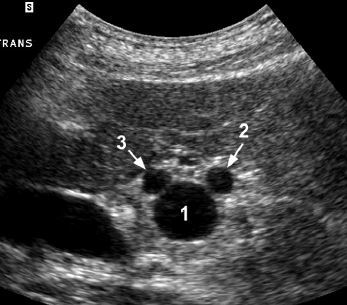

A

1. portal vein

2. proper hepatic artery

3. CBD